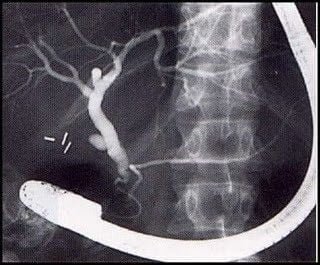

Abdomen, aparato digestivo y via biliarTécnicas de Exploración Radiológica Imágenes del estudio de las vias biliares 10 julio, 2012 Tidito Algunas imágenes de los distintos estudios de las vías biliares:Colangiografías: Colangiopancreatografía retrógrada endoscópica Colangiografía intraoperatoria: